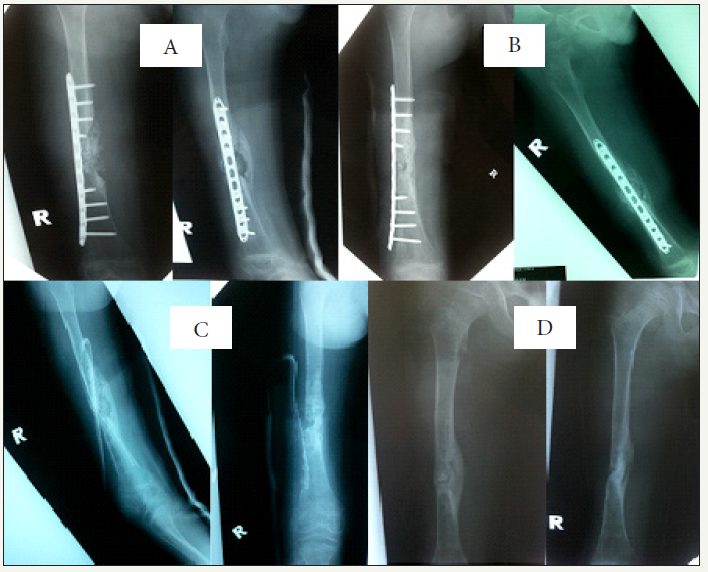

Figure 1: Serial radiographs of the patient’s right femur in anteroposterior (AP) and lateral views:

1a: Day 1 post-external fixation;

1b: Osteomyelitic changes of the right femur 2 months post-trauma;

1c: Post-wound debridement, bone resection and external fixator removal;

1d: The fracture site was mobile even though there was medial bridging callus seen on the radiographs at 6 months post-trauma.

XY, an 8-year-old boy, sustained an open fracture of the right femur grade IIIa in a motor vehicle accident. The patient presented late to the hospital and hence intravenous antibiotics (cefuroxime and metronidazole) were started 4 hours post-trauma. Wound debridement and external fixation (Figure 1a) of the fracture were done more than 12 hours post-trauma. He was given 2 weeks of intravenous antibiotics in ward and was then discharged home well. Wound coverage with split skin graft was done 1-month posttrauma.

Post-trauma 2 months, persistent serous discharge was noted from the pin sites. The child was afebrile. Radiographs of the right femur showed osteomyelitic changes at the pin sites (Figure 1b). The child was then treated with intravenous cloxacillin and fusidic acid. Wound debridement, external fixator removal and infected bone resection were done. Skeletal traction via a right calcaneal pin was applied. Bone tissue culture revealed a heavy growth of Staphylococcus aureus. The antibiotics were given for a total duration of 6 weeks (2 weeks intravenously and 4 weeks via oral route). The right lower limb skeletal traction and calcaneal pin were removed 6 weeks after insertion and a right lower limb full-length thermoplastic splint was applied (Figure 1c). The child was active, ambulating via wheelchair upon discharge with his erythrocyte sedimentation ratio (ESR) improved from 34 to 4mm/hr and white blood cell (WBC) count from 15.23 to 6.1x109/L.

During review at six months post-trauma, examination showed a right lower limb shortening of 3cm and the fracture site was mobile even though there was medial bridging callus seen on the radiographs (Figure 1d). The wound was clean and septic parameters were normal (ESR 6mm/hr, WBC 9.3x109/L). We decided to put a temporary 8-holes 3.5mm straight locking plate and 5mL synthetic bone graft to hasten the union of the fracture and to reduce the true shortening (Figure 2a). Acute distraction of 2cm was done intra-operatively to reduce the true shortening to 1cm compared to the contralateral lower limb. The child was given another 2 weeks of oral cloxacillin post-operation with daily wound dressing.